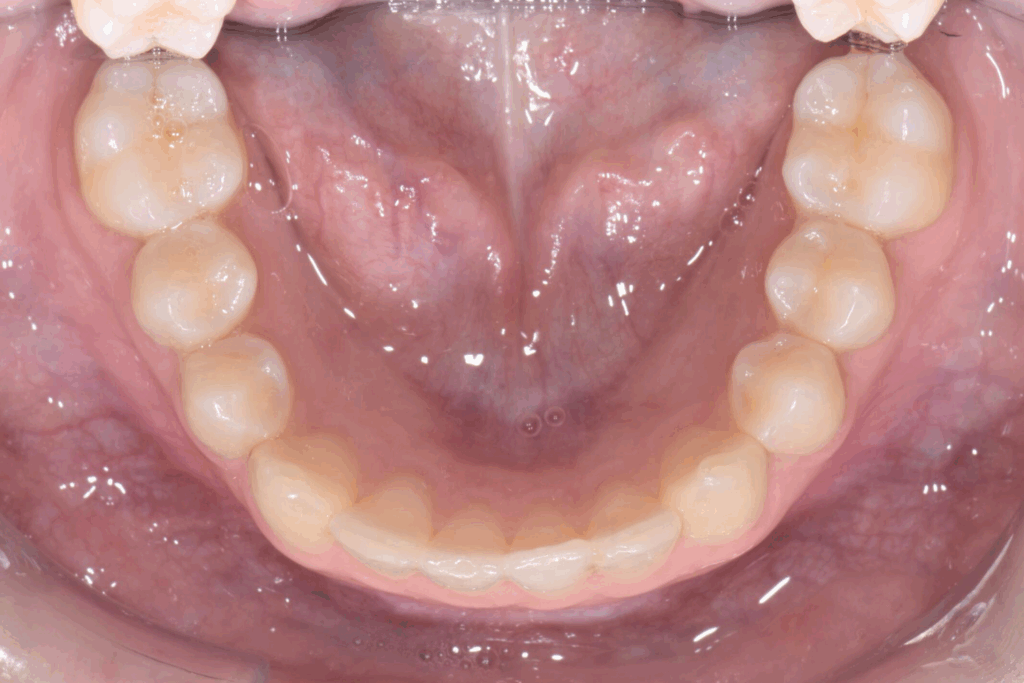

La prima fase del trattamento è stata un’analisi approfondita. Durante il check-up, abbiamo confermato la diagnosi di agenesia dei secondi molari permanenti inferiori, una condizione congenita che lascia spazi vuoti nell’arcata. Abbiamo inoltre rilevato che gli incisivi superiori erano di dimensioni ridotte rispetto al resto dei denti e che la paziente presentava un morso profondo, con gli incisivi superiori che coprivano eccessivamente quelli inferiori. Questa valutazione completa ci ha permesso di creare un piano di trattamento personalizzato e preciso, tenendo conto di tutte le problematiche presenti.

- Chiusura degli spazi: gli allineatori sono stati programmati per spostare i denti posteriori e chiudere gli spazi vuoti lasciati dall’agenesia dei settimi, evitando la necessità di impianti o ponti.

Una volta completata la fase ortodontica, siamo passati alla finalizzazione estetica degli incisivi superiori. Utilizzando la tecnica della ricostruzione in composito, abbiamo aumentato le dimensioni dei denti, migliorandone la forma e l’armonia con il resto del sorriso. Il composito, un materiale estetico e versatile, ci ha permesso di ottenere un risultato naturale e duraturo senza sacrificare la struttura dentale originale.